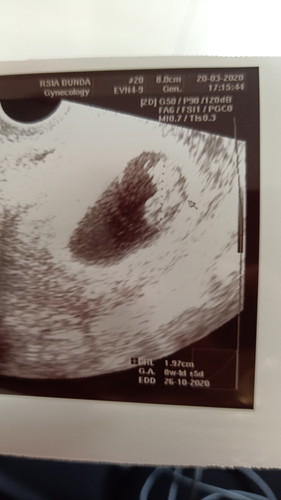

Selamat malam mom, ada yang bisa bantu baca hasil usg ?

Kemarin saya usg, tapi tdk diberikan penjelasan oleh dokternya bagaimana kondisi bayi saya, apakah beratnya sdh pas dgn minggunya, apakah ketuban saya bagus atau penjelasan lainnya. Mohon bantuannya mom??